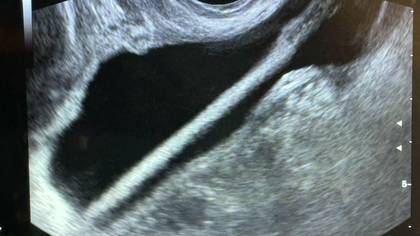

Врачи Красногорской больницы спасли 46-летнюю пациентку, достав из ее мочевого пузыря косметический карандаш. Об этом в среду, 11 февраля, сообщила пресс-служба Министерства здравоохранения Московской области.

Как сообщил заведующий урологическим отделением Красногорской больницы Петр Сысоев, женщине сделали УЗИ, после этого провели операцию, в ходе которой удалили карандаш с помощью эндоскопа.